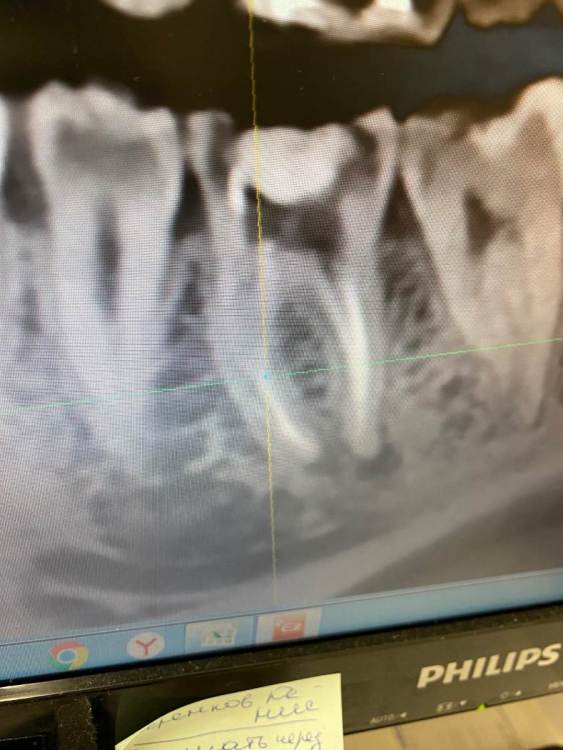

Нижняя шестерка. Удаляли нервы 4 года назад. Месяц назад заболел зуб(больно было давить на него)и кушать что то твердое.

пошла к стоматологу(сделала прицельный снимок,сказала периодонтит)

Вскрыла пломбу,распломбировала каналы.почистила, положила лекарство. Зуб

Все равно болел.

пришла во второй раз, поменяли лекарство,та же картина. Я сделала кт. Врач сказала на снимке киста. Положила лекарство. Не помогает. Подскажите что делать с таким зубом???

A501F1B5-4E2D-42AE-84CD-DA5A1A931FF5.jpeg

На зубе на самом деле "киста"

я бы советовал лечение, второй вариант, если не получится - удаление